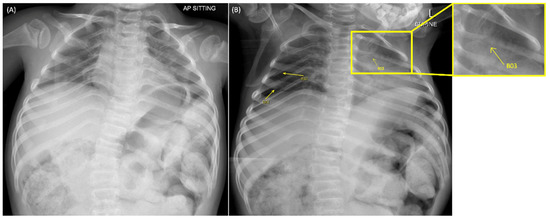

2. Case Presentation